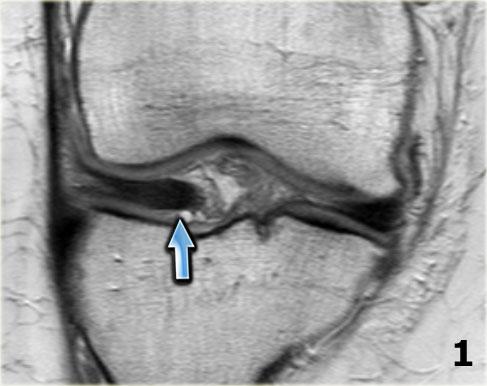

Dấu hiệu PCL đôi

Dấu hiệu dây chằng chéo sau (PCL) đôi là một dải giảm tín hiệu nằm song song và ở phía trước-dưới so với PCL trên ảnh MRI mặt phẳng đứng dọc.

Đây là dấu hiệu có độ đặc hiệu cao trong chẩn đoán rách sụn chêm kiểu quai xô (3).